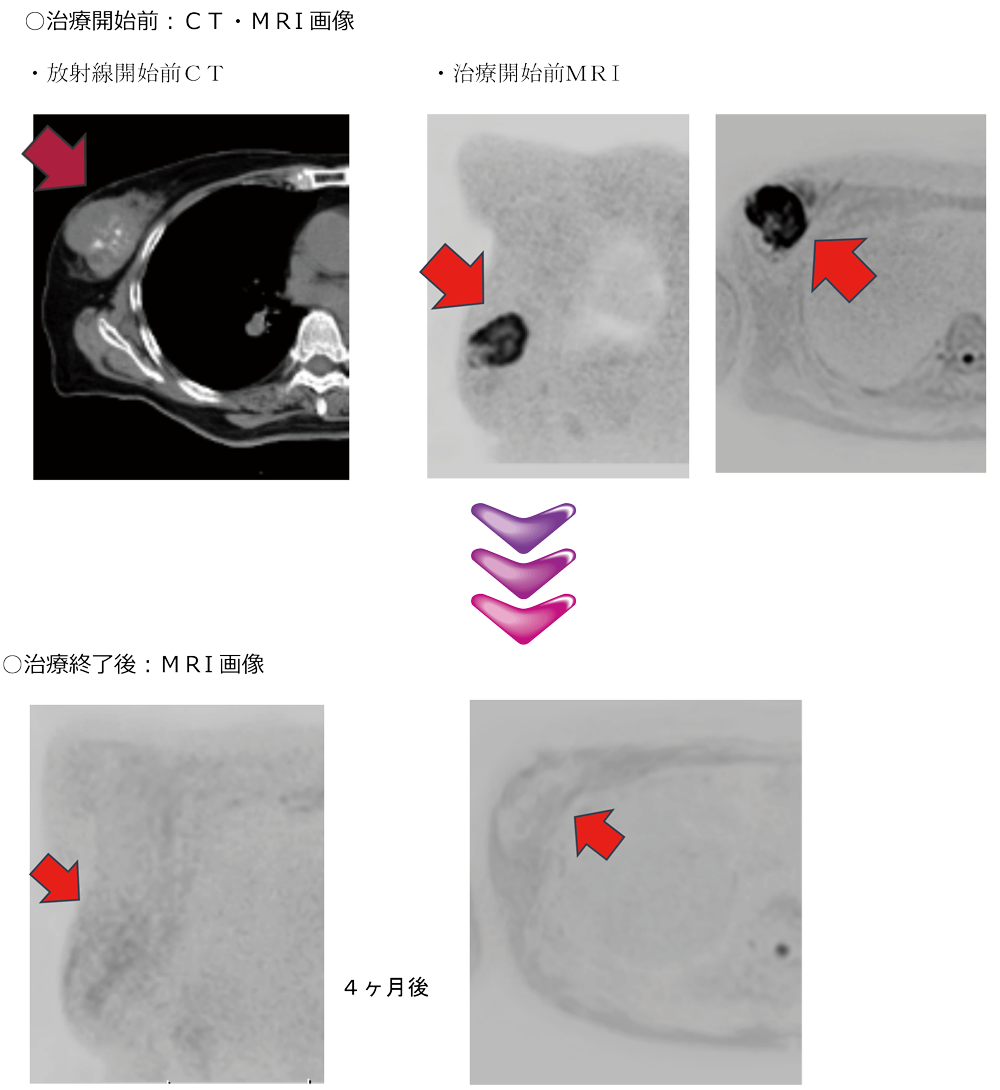

生まれのブランドで I19-175 2017年第10号10月号 臨床放射線 臨床医学